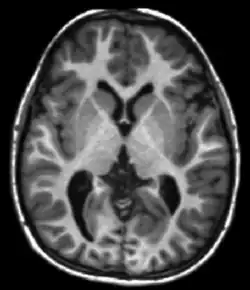

Neuroimaging

MRI diffusion tensor imaging of white matter tracts

MRI is the investigative tool of choice for neurological cancers over CT, as it offers better visualization of the posterior cranial fossa, containing the brainstem and the cerebellum. The contrast provided between grey and white matter makes MRI the best choice for many conditions of the central nervous system, including demyelinating diseases, dementia, cerebrovascular disease, infectious diseases, Alzheimer's disease and epilepsy.[31][32][33] Since multiple images are taken milliseconds apart, it can show how the brain responds to different stimuli, enabling researchers to study both functional and structural brain abnormalities in psychological disorders.[34] MRI also is used in guided stereotactic surgery and radiosurgery for treatment of intracranial tumors, arteriovenous malformations, and other surgically treatable conditions using a device known as the N-localizer.[35][36][37] New tools that implement artificial intelligence in healthcare have demonstrated higher image quality and morphometric analysis in neuroimaging with the application of a denoising system.[38]

The record for the highest spatial resolution of a whole intact brain (postmortem) is 100 microns, from Massachusetts General Hospital. The data was published in Nature in October 2019.[39][40]

Though MRI is used widely in research on mental disabilities, based on a 2024 systematic literature review and meta analysis commissioned by the Patient-Centered Outcomes Research Institute (PCORI), available research using MRI scans to diagnose ADHD showed great variability.[41] The authors conclude that MRI cannot be reliably used to assist in making a clinical diagnosis of ADHD.[41]